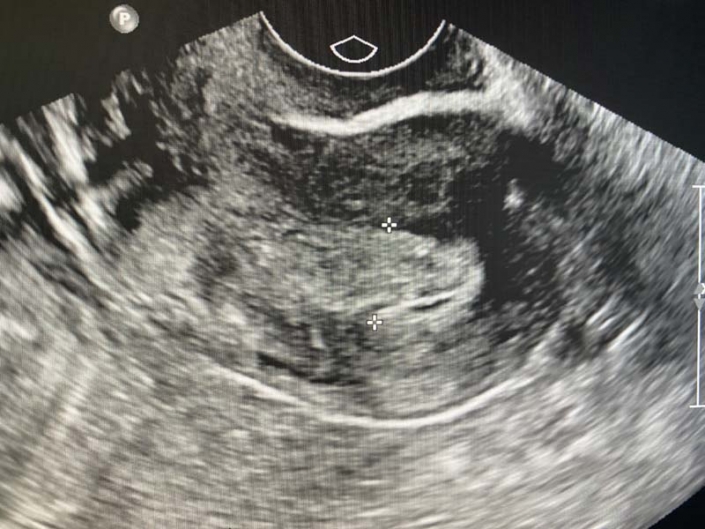

Transvaginal image definitively depicting the interstitial gestational

Thickened endometrium is seen with no pregnancy sac in the uterine Thickened Endometrium But No Gestational Sac I have very mild bleeding for the past two days and slight press on my right. If the gestational sac —which encloses the developing baby and contains amniotic fluid—isn't visible by around five weeks gestation, it. Thickened endometrium is a condition where the lining of the womb (uterus) becomes abnormally thick, even when. The condition is not cancer. Endometrial thickness. Thickened Endometrium But No Gestational Sac.